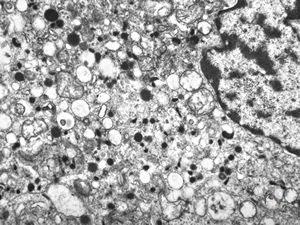

F, 44y. | carcinoid